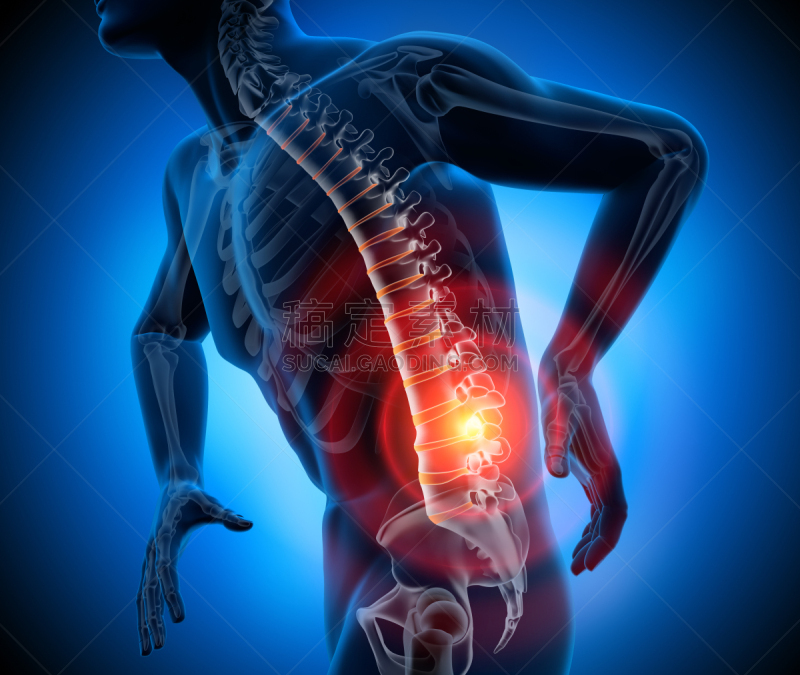

背部剧烈疼痛的男人详情

JPG